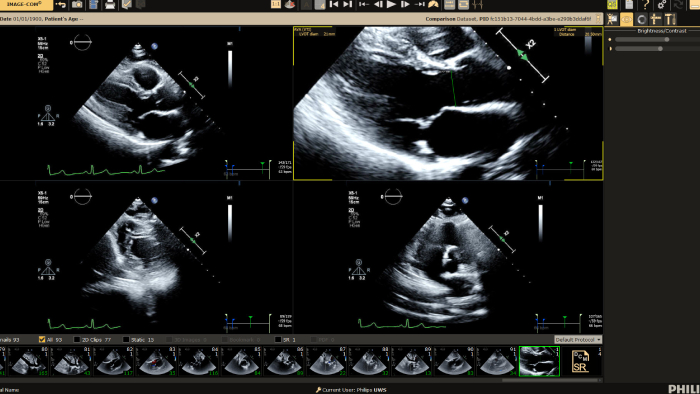

We thank all who were able to attend this year’s European Society of Cardiology programs, including the hands-on workshop sessions, expert symposium on innovations in cardiac imaging workflow, and a friendly open echo skills competition using LifeTec’s Cardiac BioSimulator, the new Philips Compact Ultrasound 5500CV system and Philips Collaboration Live tele-ultrasound.

You can still access recordings of 4 full days of hands-on workshops about best practices in multimodality cardiac imaging with expert teams. See first-time-right imaging for cardiac care, including valvular and related diseases, cardiomyopathies, and intracardiac masses and cardiac tumors.